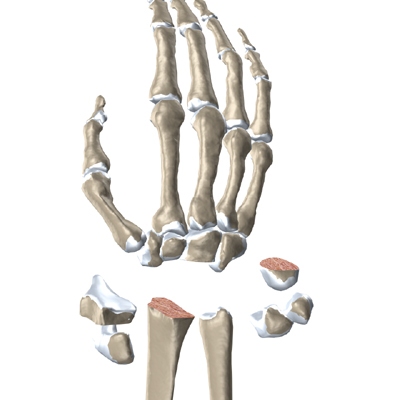

The anatomy of the wrist joint is extremely complex, probably the most complex of all the joints in the body. The wrist joint is actually made up of many joints and many bones. These joints and bones let us use our hands in many ways. The wrist must be extremely mobile to give our hands a full range of motion. At the same time, the wrist must provide the strength for heavy gripping.

The wrist is made up of eight separate small bones, called the carpal bones. The carpal bones connect the two bones of the forearm, the radius and the ulna, to the bones of the hand. The metacarpal bones are the long bones that lie mostly underneath the palm. The metacarpals are in turn attached to the phalanges (the bones in the fingers and thumb).

Modern artificial wrist joints are made of metal and plastic. The part that fits against the end of the radius bone of the forearm is called the radial component. It is made up of two pieces. A flat metal piece is placed on the front part of the radius. It has a stem that attaches down into the canal of the bone. A plastic cup fits onto the metal piece, forming a socket for the artificial wrist joint.

The part that replaces the small wrist bones is called the distal component. This piece is made completely of metal. It is globe shaped to fit into the plastic socket on the end of the radius. The metal distal component is attached by two metal stems that fit into the hollow bone marrow cavities of the carpal and metacarpal bones of the hand.

The plastic used in artificial joints is tough and slick. It allows the two pieces of the new joint to glide easily against each other as you move your wrist. The ball and socket allow movement of the wrist in all directions.

The surgeon needs to make room for the artificial joint. To do this, most of the first row of:

Carpal Bones are Removed

from the wrist. The end of the radius is also shaped to fit the prosthesis.